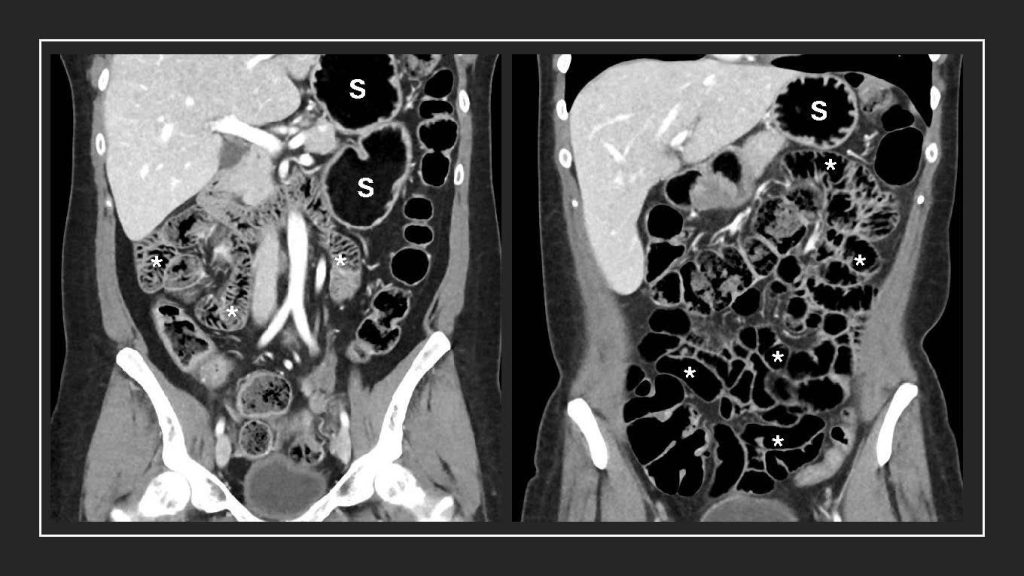

ROCHESTER, Minn. — In a new pilot feasibility study, researchers from Mayo Clinic, the University of Washington School of Medicine, the University of California San Francisco, and Nextrast Inc. found that a new imaging oral agent, also known as a "contrast agent," helps radiologists better see bowel structures and disease in CT imaging when compared with the current oral contrast agents.

"We carefully designed this new class of oral contrast agent to overcome many of the diagnostic shortcomings of existing contrast agents for a broad range of diseases," says Benjamin Yeh, M.D., a co-author on the study, radiologist at the University of California at San Francisco and co-founder of Nextrast, which created the new agent. "The Clinical Phase 2 results confirm that our dark agent can reveal previously impossible-to-detect findings, including very small bowel tumors and subtle inflammatory conditions that are often missed with conventional agents at CT."

In their paper, the authors report findings that suggest this new agent significantly improves visualization of inflammatory bowel disease (IBD) or cancer within the abdomen, and may provide earlier and more confident diagnoses.

The study compared CT scans of 32 patients with the dark borosilicate oral contrast agent and scans with conventional water or iodine-based oral contrast agents, to look at anatomical structures and disease presence.

Evaluators identified clinically relevant findings in seven patients that were not detected using the standard contrast.

"CT scans performed with the new agent will likely do a better job of displaying pathologies in the stomach and proximal small bowel, areas where CT with traditional oral contrast performs poorly," Dr. Fletcher says. "Pathologies within the lumen will be better displayed because the lumen is more distended, and the brightness of the pathologies on the CT images will be increased, making them more conspicuous.”